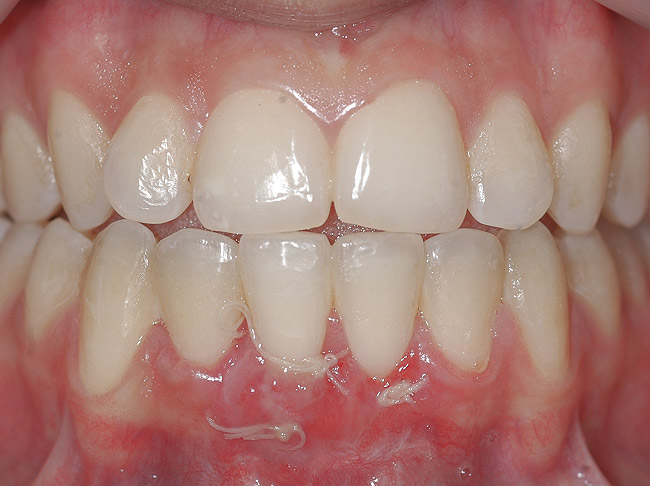

Fig 15. Same patient 2 years later showing worsening of GR and inflammation.

Figure 15